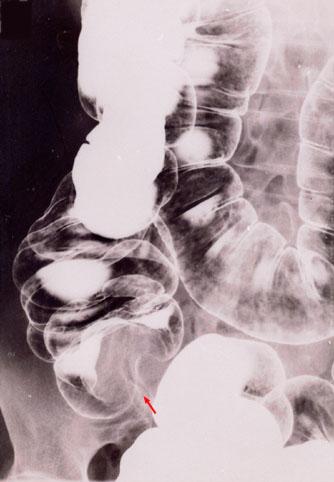

Relatively typical mucinous cystadenocarcinoma of the appendix (malignant mucocele)

[ Image ID:3895 ]

Appendix/Mucinous cystadenocarcinoma

Large intestine(Colon)/Appendix

Technique, Method

X-ray

Size

40 -